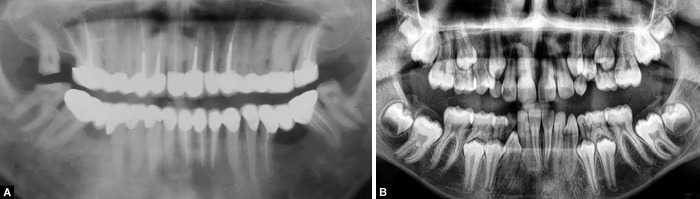

Case description: This article highlights the first ever reported case of familial, nonsyndromic, generalized radiculomegaly affecting the primary and permanent dentitions in a 13-year-old male who had visited the Department of Pedodontics and Preventive Dentistry for a dental checkup. Clinical examination revealed a delay in eruption since his dentition was inconsistent with his age. An orthopantomograph showed the presence of primary and permanent teeth with longer roots than usual.

Conclusion: A diagnosis of radiculomegaly was made from full-mouth CBCT tooth measurements that confirmed longer roots. Orthopantomographs of his sibling and father revealed similar findings.